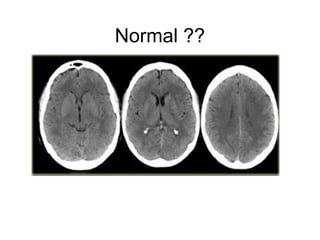

Normal ??

CT Perfusion